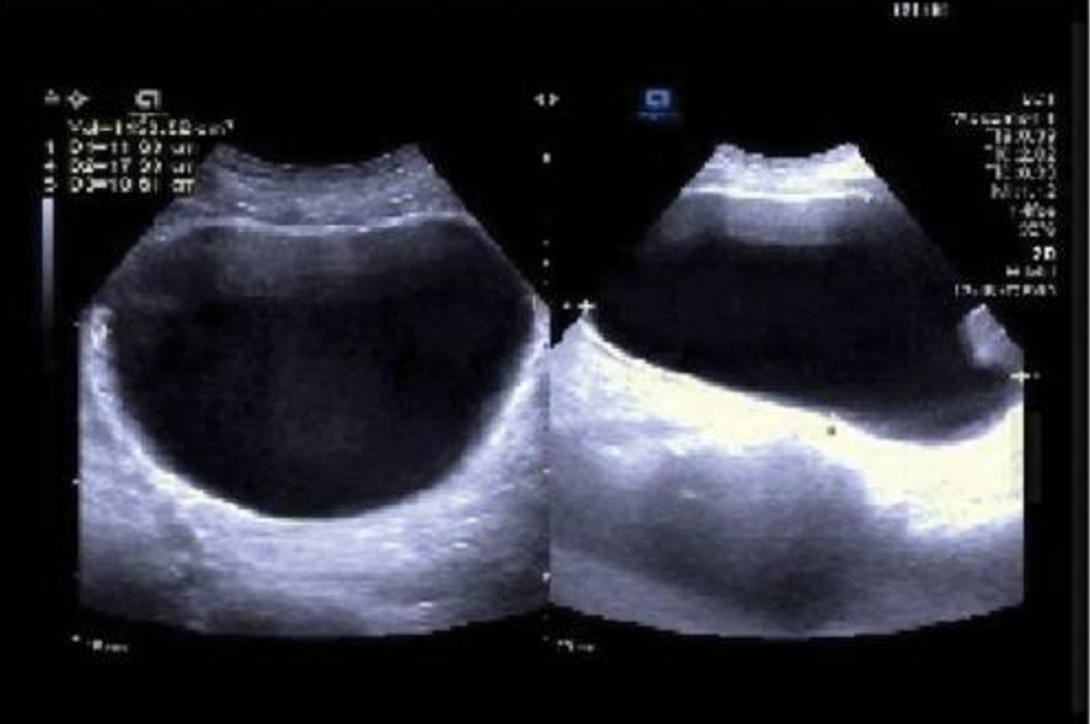

患者入院前提示VZV阳性。实验室检查包括生化分析、全血计数、血清免疫球蛋白(IgG、IgA和IgM)、传染病筛查和粪便检查均正常。血清前列腺特异性总抗原(TPSA):4.07µg/L。尿液分析和尿液细菌培养(-);泌尿系统多普勒超声显示:前列腺大小正常(3.9厘米*2.9厘米*2.6 cm);排尿后膀胱残余尿液:1153 mL(图1) ;2022年7月27日的尿动力学检查结果表明:排尿期间未发现逼尿肌收缩,排尿方式为腹压辅助排尿,多次尝试均无尿排出。提示膀胱逼尿肌收缩无力;残余尿液提示膀胱排空严重受损(图2)。大脑、腰椎和骶骨的磁共振成像(MRI)、心电图、胸部CT和上腹部的多普勒超声均未显示明显异常。

图1 尿路多普勒超声显示:前列腺大小正常(3.9厘米*2.9厘米*2.6 cm);排尿后膀胱残余尿液:1153 mL